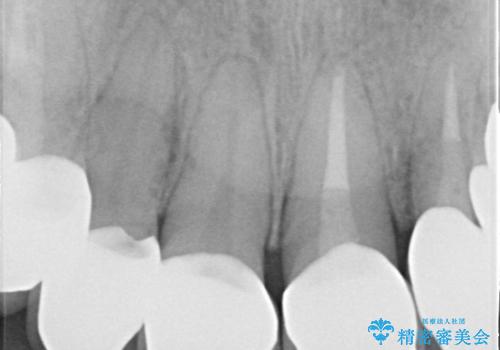

セラミックのかぶせ物だけで、歯並びまで変えようとするのには限界があります。

今回矯正治療で歯並びを整えた後に、セラミックを装着することにより、審美的・機能的に優れた仕上がりにすることができました。